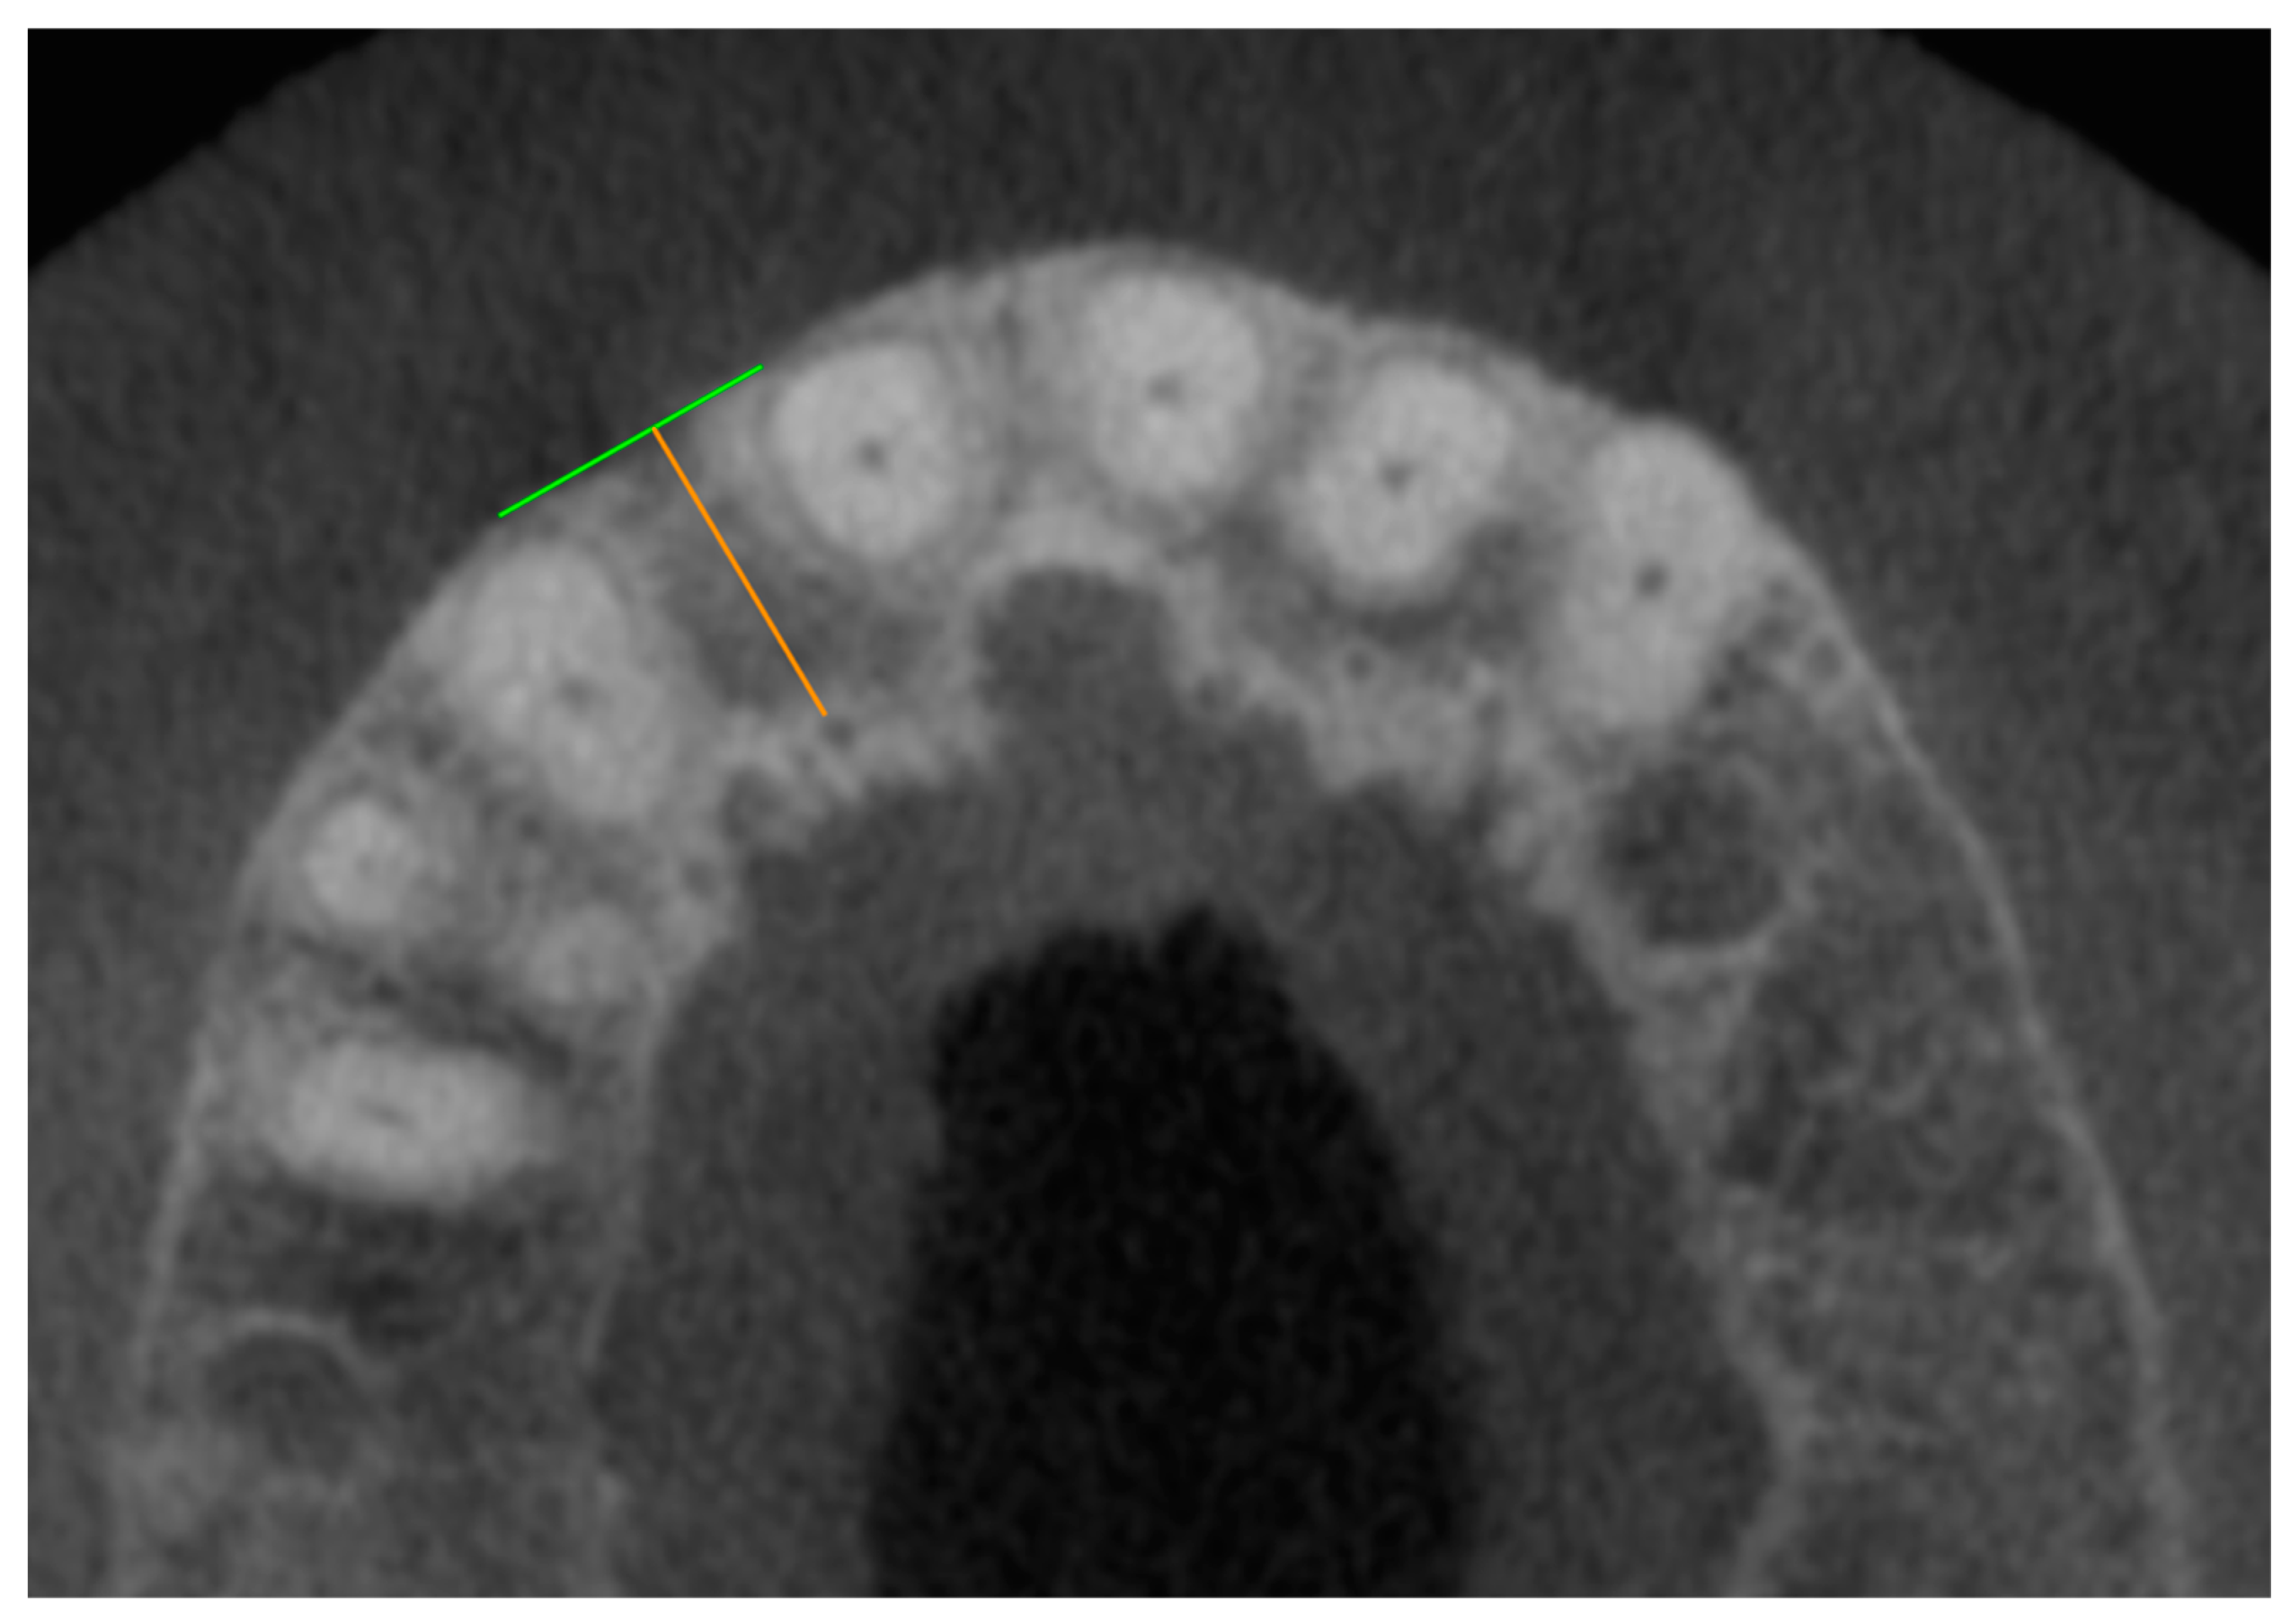

For the measurements, all foramina between the first premolars (teeth 14–24) were taken into account in the axial plane. The foramen to be measured was coded in the axial plane using an assigned number (Figure 1).

Figure 3. CBCT dataset with the axial representation of an accessory foramen of the canalis sinuosus palatal to missing tooth 12. The green line forms a clearly recognizable outer cortex of the alveolar ridge as an endpoint of the orange measuring section, which begins at the outer edge of the foramen.